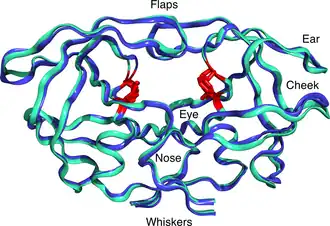

Mature HIV protease exists as a 22 kDa homodimer, with each subunit made up of 99 amino acids.[1] A single active site lies between the identical subunits and has the characteristic Asp-Thr-Gly (Asp25, Thr26 and Gly27) catalytic triad sequence common to aspartic proteases.[8] As HIV-1 PR can only function as a dimer, the mature protease contains two Asp25 amino acids, one from each monomer, that act in conjunction with each other as the catalytic residues.[9] Additionally, HIV protease has two molecular "flaps" which move a distance of up to 7 Å when the enzyme becomes associated with a substrate.[10] This can be visualized with animations of the flaps opening and closing.

Two types of mutations are generally associated with increasing drug resistance: "major" mutations and "secondary" mutations. Major mutations involve a mutation on the active site of HIV-1 PR, preventing the selective inhibitors from binding it. Secondary mutations refer to molecular changes on the periphery of the enzyme due to prolonged exposure of similar chemicals, potentially affecting inhibitor specificity for HIV-1 PR.[3]